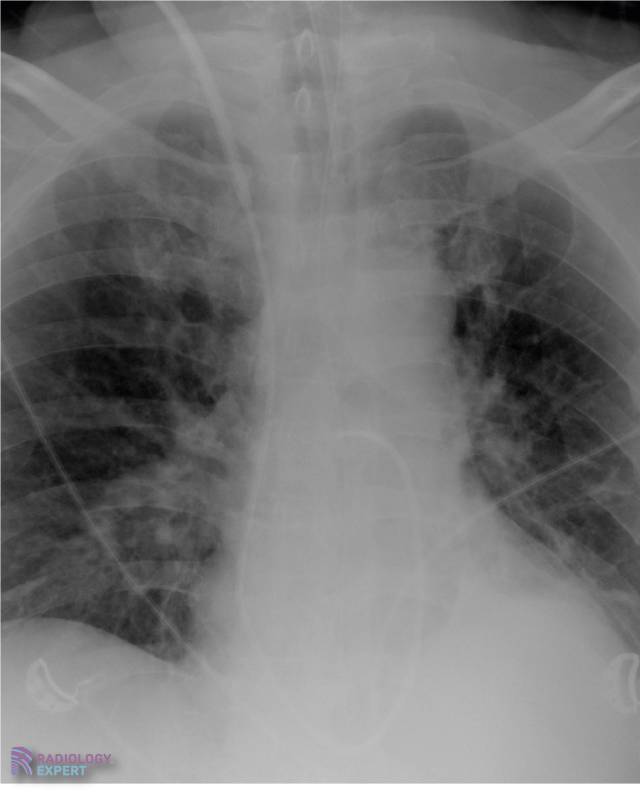

X-Thorax IC

De basis principes van het X-thorax onderzoek bij een IC patient.

Swan-Ganz catheter via de v. jugularis rechts met de tip proximaal in de rechter a. pulmonalis. Swan-Ganz catheter via de v. jugularis rechts met de tip proximaal in de rechter a. pulmonalis.